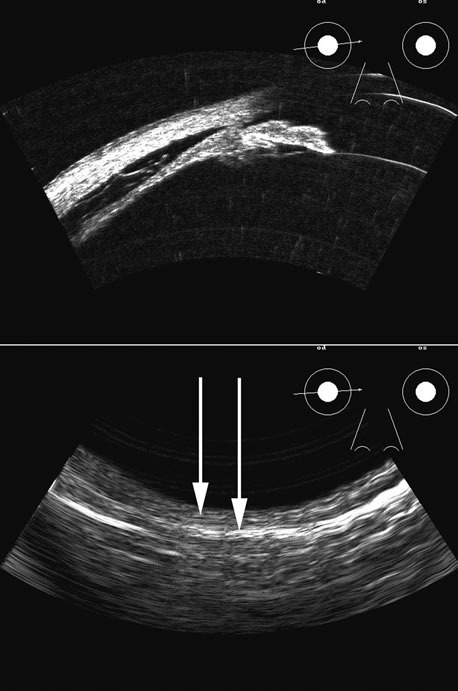

Fig. 17. This patient with a Molteno tube was treated for glaucoma. The top 50 MHz B-scan clearly shows the Molteno Tube (arrow). The bottom 10 MHz B-scan of the same patient demonstrates a choroidal detachment (large arrow) with associated posterior retinal detachment (small arrow). Choroidal elevations are typically convex, highly reflective surfaces with posterior limitation at the vortex vessels. Retina will always attach at the optic nerve. Choroidal elevations are often noted in several quadrants, as seen here.